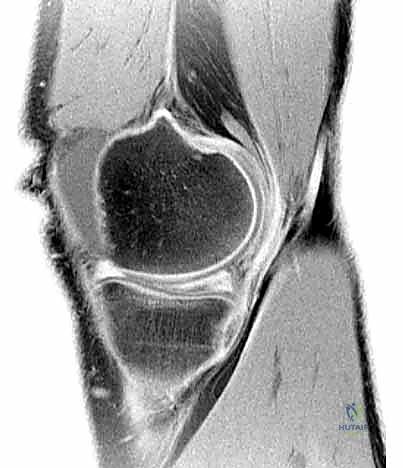

- التصوير بالرنين المغناطيسي (MRI): هو المعيار الذهبي (Gold Standard) لتشخيص تمزقات الغضروف الهلالي. يوفر صوراً ثلاثية الأبعاد وعالية الدقة للأنسجة الرخوة. من خلال الرنين، يستطيع الدكتور هطيف تحديد نوع التمزق، حجمه، موقعه (في أي منطقة دموية)، وما إذا كانت هناك إصابات مصاحبة (مثل تمزق الرباط الصليبي الأمامي ACL).